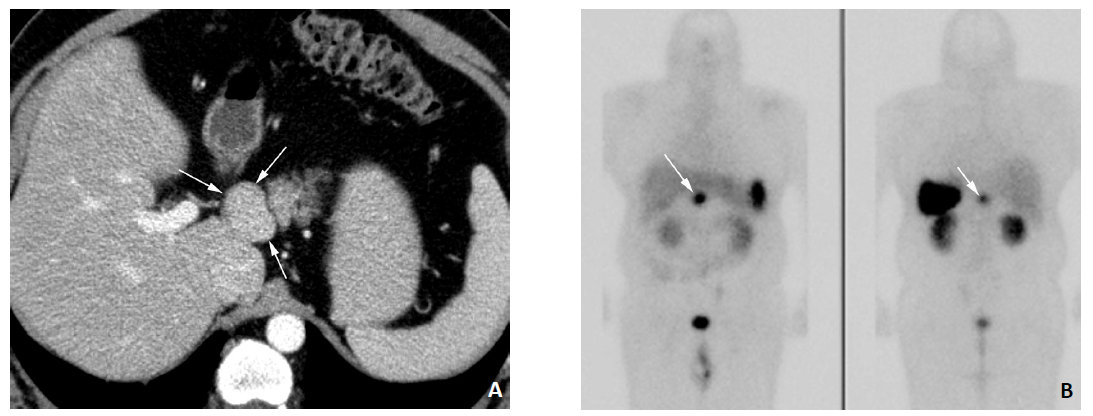

Симптом золлингера эллисона что это

Симптом золлингера эллисона что это 103 фото